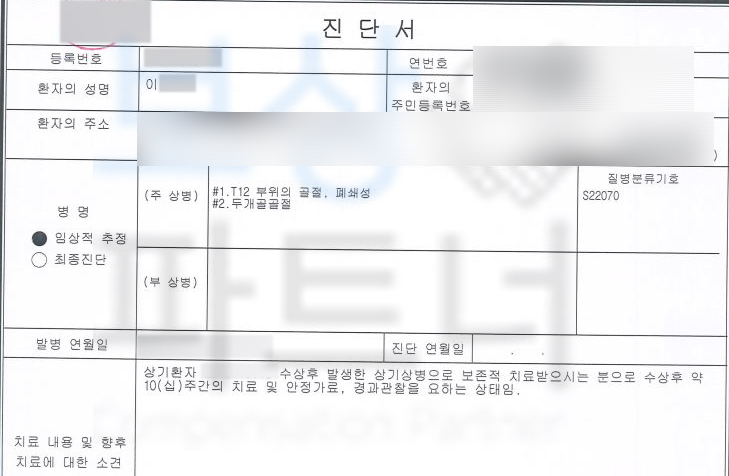

당시 극심한 허리 통증에 며칠 쉬면 나아질 줄 알았지만 시간이 지나도 사라지지 않는 통증에 병원에 내원하여 정밀검사를 받으셨는데요, 그렇게 진단받은 상병은

12번 흉추의 골절 S220

위 진단으로 이@@님은 최소 10주간 TLSO 보조기 즉 허리보조기를 착용하시며 요양하셔야 했습니다. 여러분들의 보험증권에 “후유장해” 항목 찾아보세요. 위 보험증권들을 보면 가입하신 보험의 기본계약에 있거나 혹은 특약으로 후유장해 보상 항목이 있습니다.

척추는 우리 몸의 중심부로서 골절이 발생하면 향후 각도 변형이나 골절로 인해 척추체의 압박률이 점점 가중되는 후유장해를 유발 할 수 있습니다.